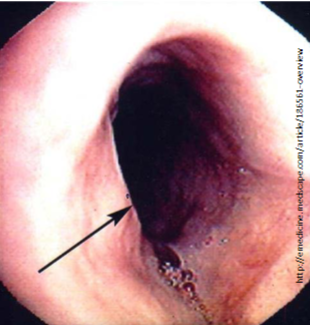

Schatzki Ring

Circumferential & thicker (includes submucosa or muscularis propria)

Usually occur in distal esophagus (immediately above or below the Squamocolumnar junction)

asymptomatic or cause sporadic dysphagia

Obstruction of esophagus by a bolus of food → crushing chest pain